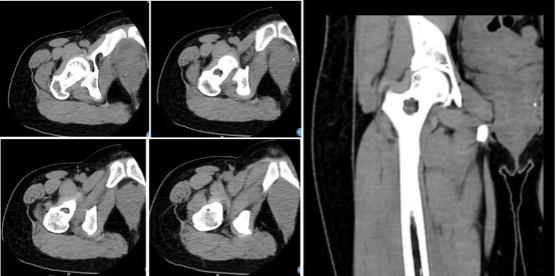

图3:CT显示病灶边界清晰,边缘樱硬化,支持良性肿瘤诊断